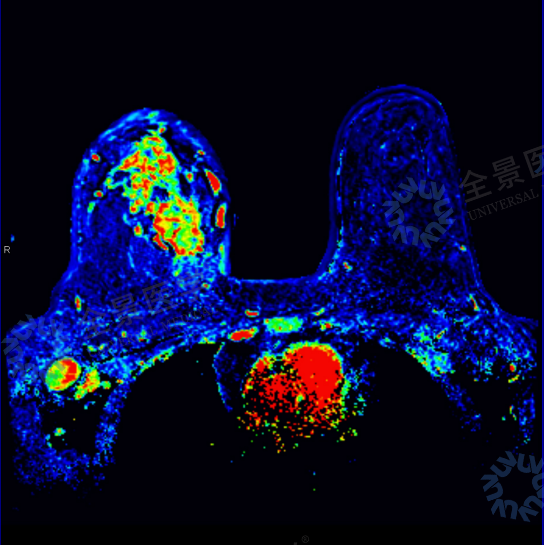

· MRI 明确为 BI-RADS 5 类,高度怀疑炎性乳腺癌,伴淋巴结转移;

邹女士的案例中,超声提示 4A 类,而 MRI 直接提示 5 类,正是影像互补价值的体现。